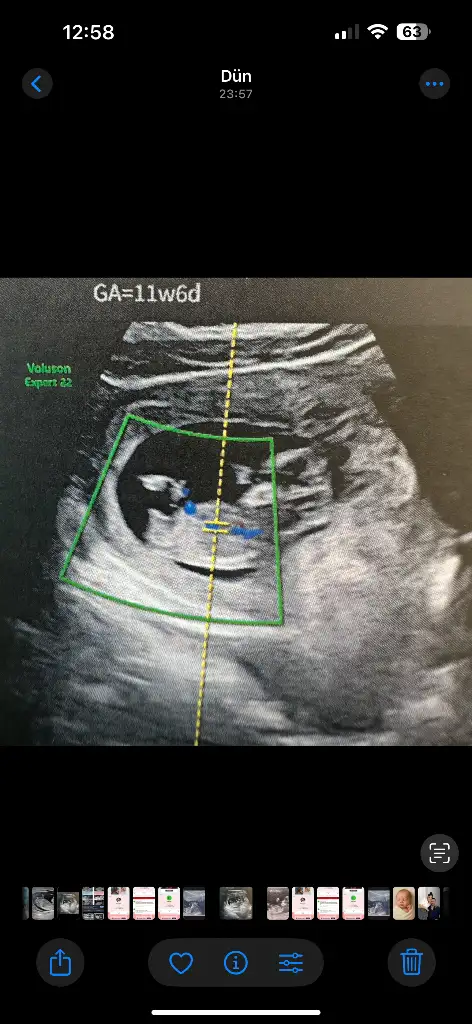

Banada tahminde bulunabilirmisiniz 10 hafta 4 günlük

Eklentiler

• IMG_20250424_145427.webp

14,1 KB · Görüntüleme: 54

• IMG_20250424_145418.webp

19,3 KB · Görüntüleme: 45

• IMG_20250424_145414.webp

18,3 KB · Görüntüleme: 55